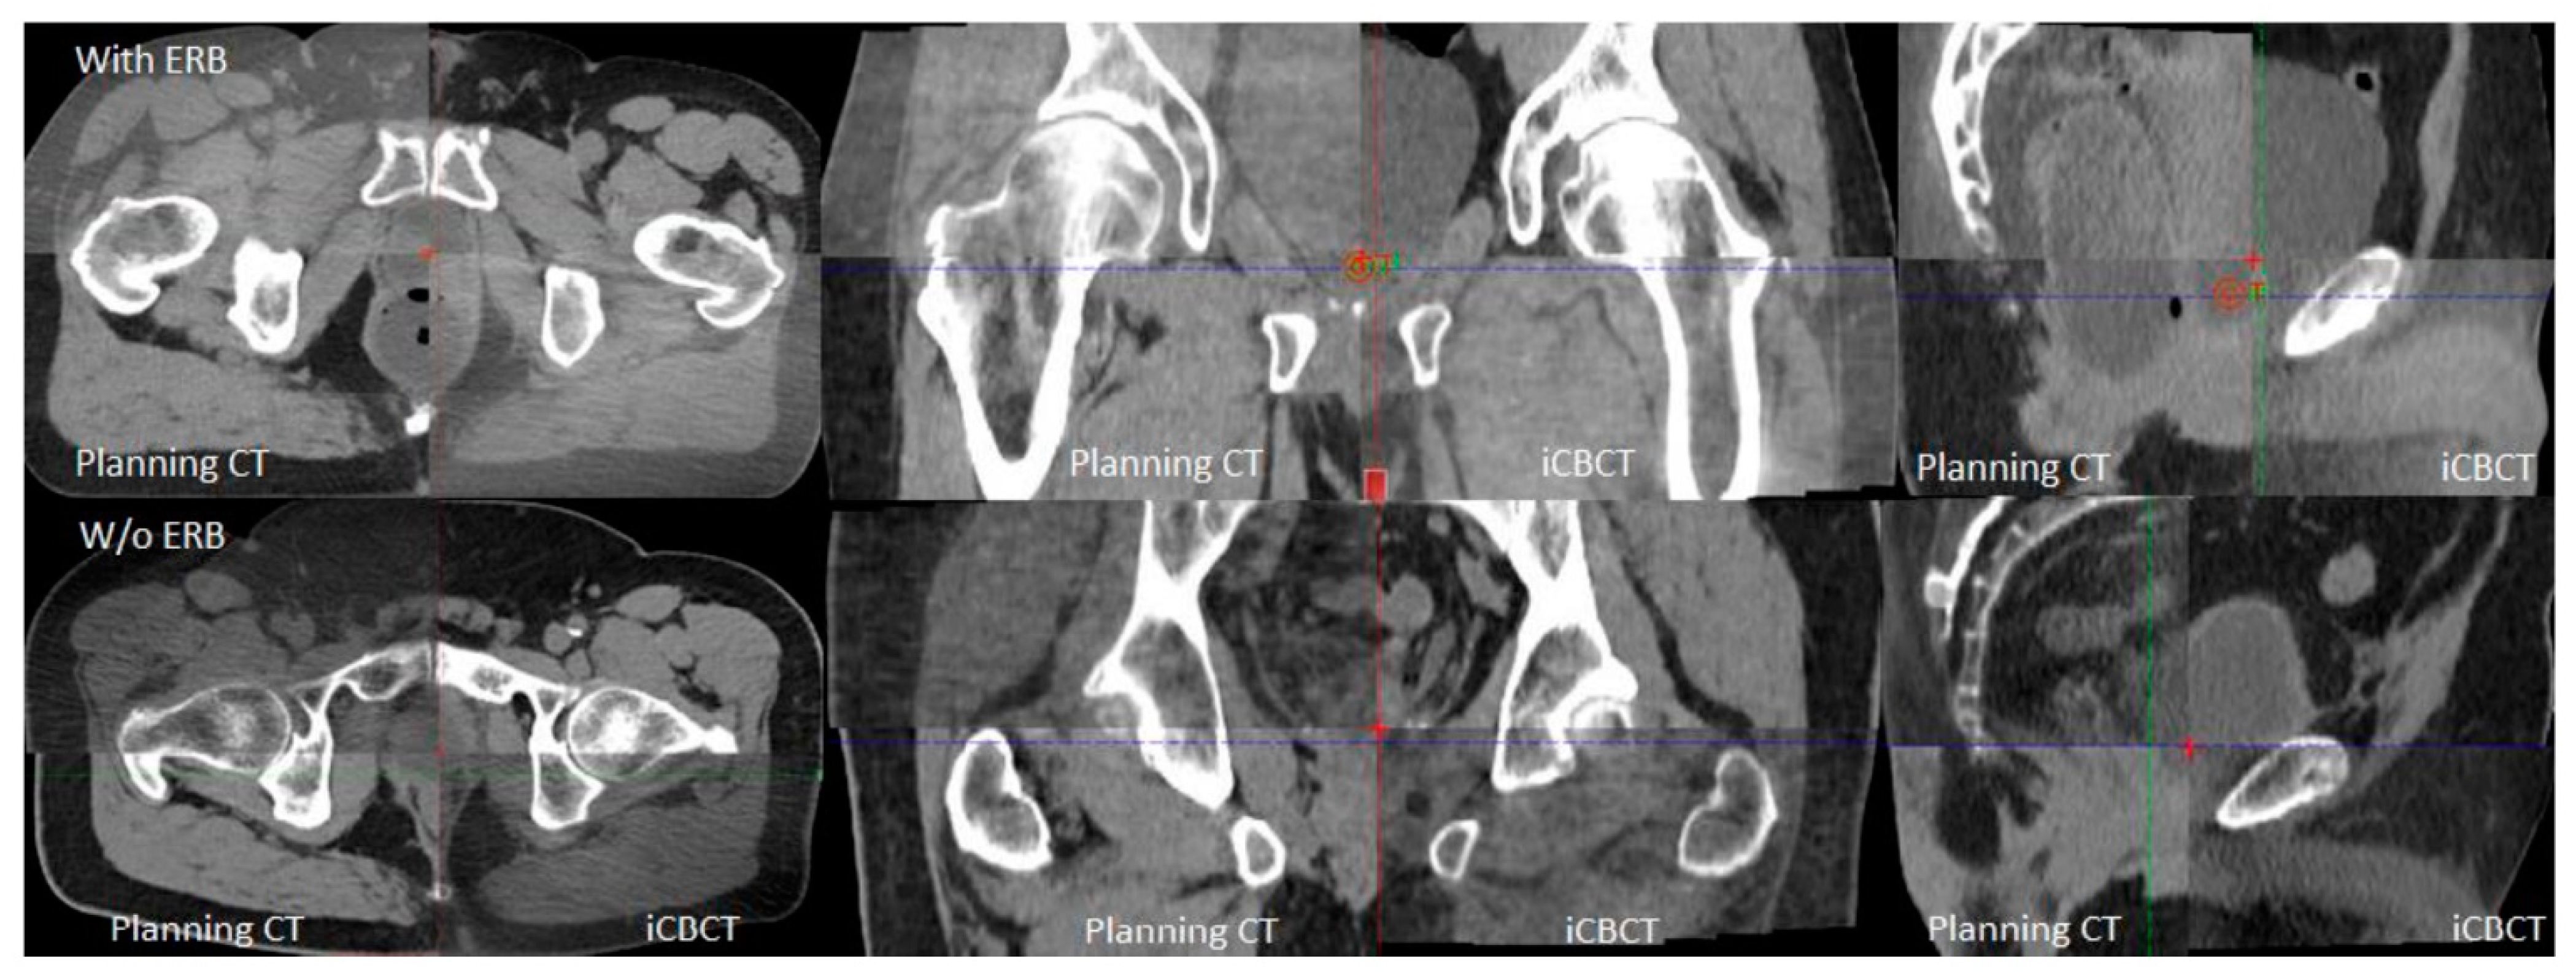

Each fraction’s iCBCT was taken prior to treatment for target localization using an On-Board Imager ® (Varian Medical Systems, Palo Alto, CA, USA) with a Pelvis Imaging mode setting (125 kVp, 1080 mAs, 900 projections, and 46.5 cm field of view) and Acuros CTS-based iterative reconstruction algorithm [21,22]. Upon confirming bladder filling by daily iCBCT, therapists then performed an automatic image registration between the planning CT and iCBCT with six degrees of freedom for couch turned on, followed by manual fine-tuning based on the rectum and bladder interfaces in axial, sagittal, and coronal views. Figure 1 provides an example of image registration accuracy using iCBCT compared to the planning CT. The rectal wall and bladder interface and the prostate bed from the obturator internus musculature in patients can be clearly differentiated on the iCBCT with and without an endorectal balloon. This soft tissue contrast quality allows therapists to accurately align the patient without seeing a solid target in a post-prostatectomy setting with clear IGRT matching instructions. Figure 2 demonstrates axial, coronal, and sagittal iCBCT reconstruction of a patient without endorectal balloon (Figure 2a–c) and with endorectal balloon (Figure 2d–f).

Figure 1.

Axial, coronal, and sagittal views demonstrating planning CT and iCBCT image guidance to identify rectal wall and bladder interface and space between bladder and obturator musculature.

Cone-beam CTs are associated with poor image quality due to the degradation caused by scattering artifacts [17,18]. The degradation in image quality makes it difficult to delineate the interface between the anterior rectal wall and the bladder. With the advancement in image guidance and more conformal radiation techniques, the omission of ERBs has become the standard of care for intact prostate and prostate bed radiotherapy receiving standard fractionation [29,30]. Additionally, patients are instructed to have a bowel movement prior to radiation treatment. Previous data have demonstrated that a distended rectum at simulation resulted in reduced toxicity but a much higher recurrence rate [31]. As the field may be moving towards hypo-fractionation, smaller target margins may be utilized. The requirements for internal organ immobilization and imaging alignment are more stringent in consideration of higher fractional doses and fewer fractions to compensate for organ motion or misalignment. Therefore, the use of an ERB may be reconsidered for organ management and better target immobilization. In the meantime, improved image quality in iCBCT provides better soft tissue contrast and Hounsfield unit uniformity [32,33]. Figure 1 and Figure 2 show examples of iCBCT for patients without and with ERB, respectively. With the clear identification of the rectal wall and bladder interface, accurate alignment can be achieved in all three views allowing the omission of daily ERB placement. The present study revisiting the use of ERBs with an improved CBCT image quality and organ consistency (i.e., bladder and rectum) is justified.